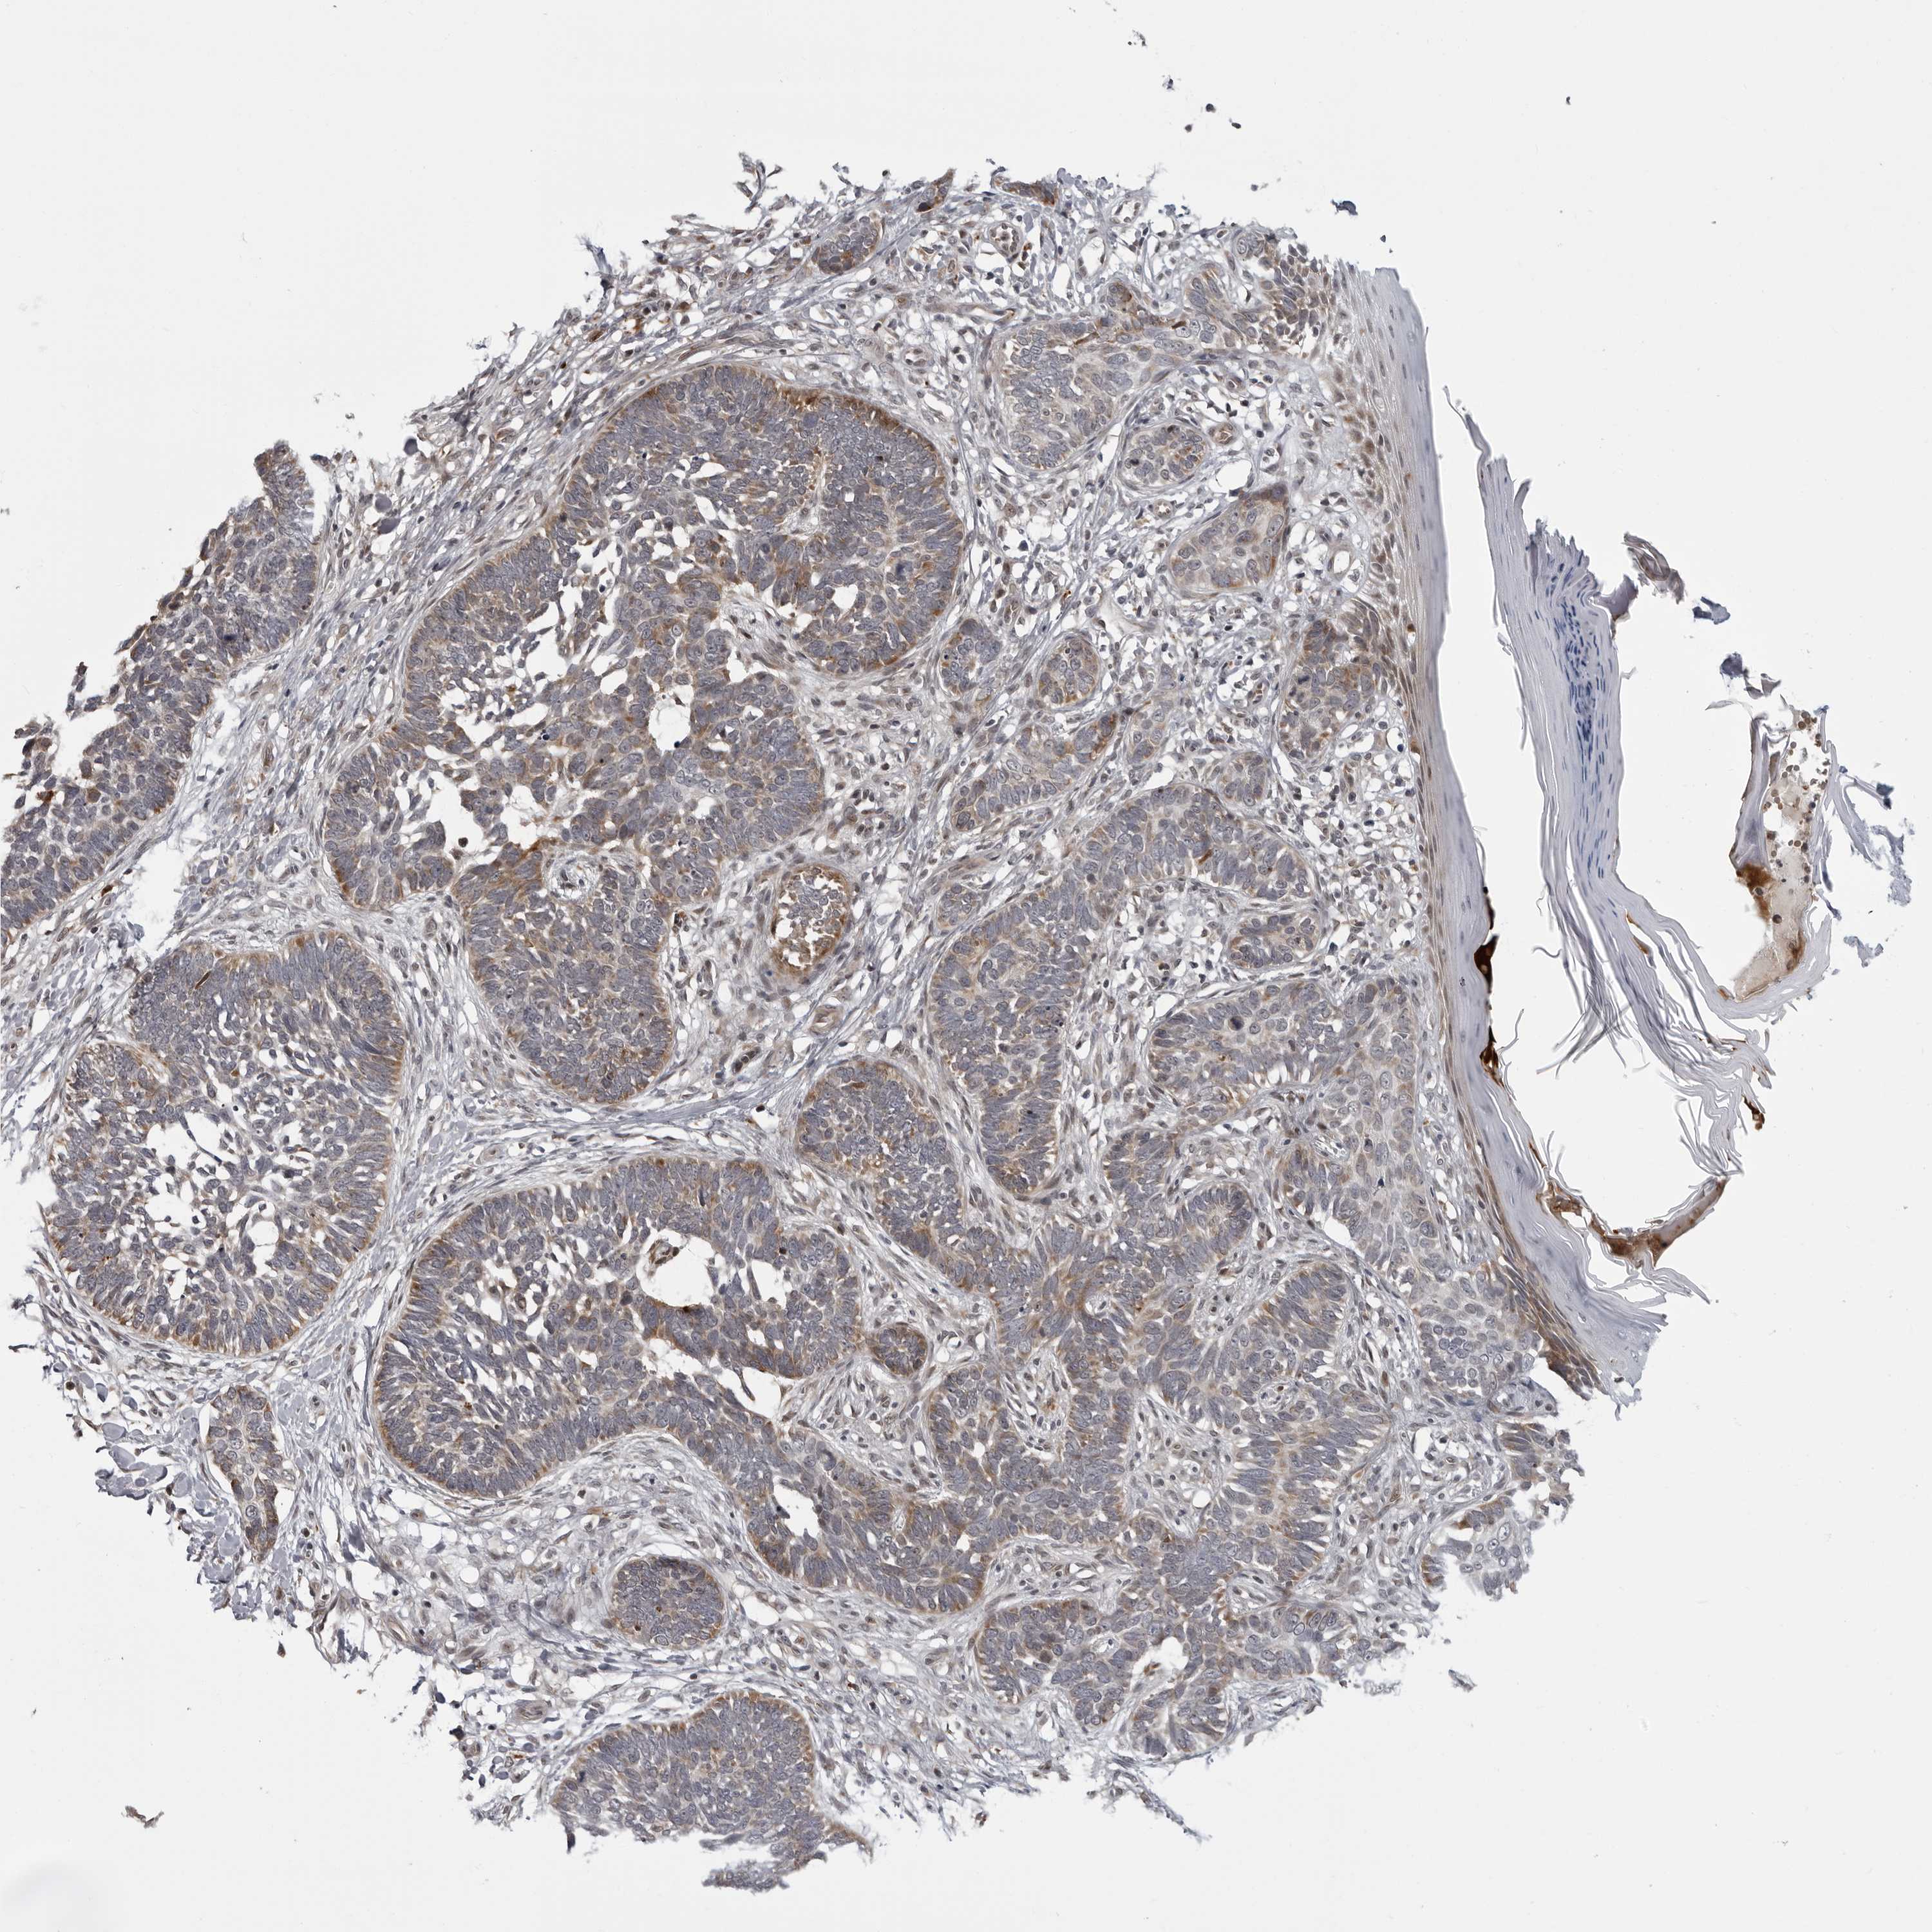

SKIN CANCER - Protein expressioni

A mouse-over function shows sample information and annotation data. Click on an image to view it in a full screen mode. Samples can be filtered based on level of antibody staining by selecting one or several of the following categories: high, medium, low and not detected. The assay and annotation is described here.

Antibody stainingi

Antibody staining in the annotated cell types in the current human tissue is reported as not detected, low, medium, or high, based on conventional immunohistochemistry profiling in selected tissues. This score is based on the combination of the staining intensity and fraction of stained cells.

Each image is clickable and will lead to virtual microscopy that enables deeper exploration of all samples and also displays staining intensity scores, fraction scores and subcellular localization as well as patient and tissue information for each sample.

Antibody HPA035262

Basal cell carcinoma